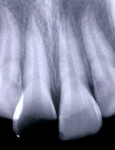

The intraoral examination showed a swollen marginal gingiva (Figure 1). The coronal fragment resembled a laminate veneer (Figure 1), and its cervical margin was slightly subgingival. Pulp vitality was checked thermally (sensitivity to cold stimulus) and confirmed with positive responses.

No alterations in the periodontal and bone tissues were observed in the radiographic examination (Figure 2). As the first clinical step, the coronal fragment and remaining root portion were cleaned with rubber cup pumice prophylaxis. There was a small area of pulpal exposure, which was partially curetted (Figure 3) and received a dressing with a commercially prepared antibiotic corticosteroid (Otosporin®, GlaxoSmithKline, www.gsk.com) for 5 minutes followed by direct pulpal capping with calcium hydroxide p.a. and a calcium hydroxide-containing cement (Hydro C, DENTSPLY, www.dentsply.com). A full-thickness flap was elevated to provide better access to the fracture line, as well as to permit the correct placement of a rubber dam and provide a clean, dry operative field. Flap elevation revealed a fracture margin ending in a 0° angle and an adequate adaptation of the coronal fragment to the remaining root portion (Figure 4). The coronal fragment and remaining root portion were then etched with 37% phosphoric acid, rinsed thoroughly, and gently air-dried. The coronal fragment was re-attached to the root remnant using an adhesive restorative technique with an etch-and-rinse adhesive system (Prime & Bond 2-1®, DENTSPLY) and a light-cured microhybrid composite resin (TPH®, DENTSPLY) (Figure 5). The restoration of the fractured crown was completed at the cervical third with resin-modified glass ionomer cement (GC Fuji II LC, GC America Inc., www.gcamerica.com) (Figure 5).